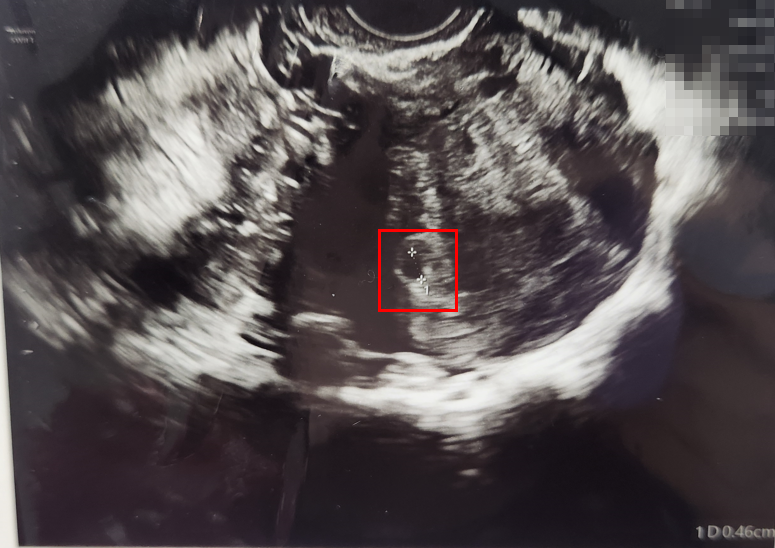

이후 초음파 검사를 진행했습니다.

두근거리는 마음으로 초음파를 확인했는데,

표시된 부분이 아기집으로 추정된다고 설명해주셨습니다.

아기집 크기는 4.6mm로 아직 많이 작다고 하셨습니다.

초음파를 꼼꼼히 확인해주신 결과, 다행히 자궁 외 임신은 아니고, 저 부분이 아기집일 가능성이 높다고 말씀해주셨습니다.

다만 크기가 작은 편이라 우려가 된다고 하셔서, 다음 주에 다시 한 번 초음파를 보기로 하고 예약을 잡고 나왔습니다.